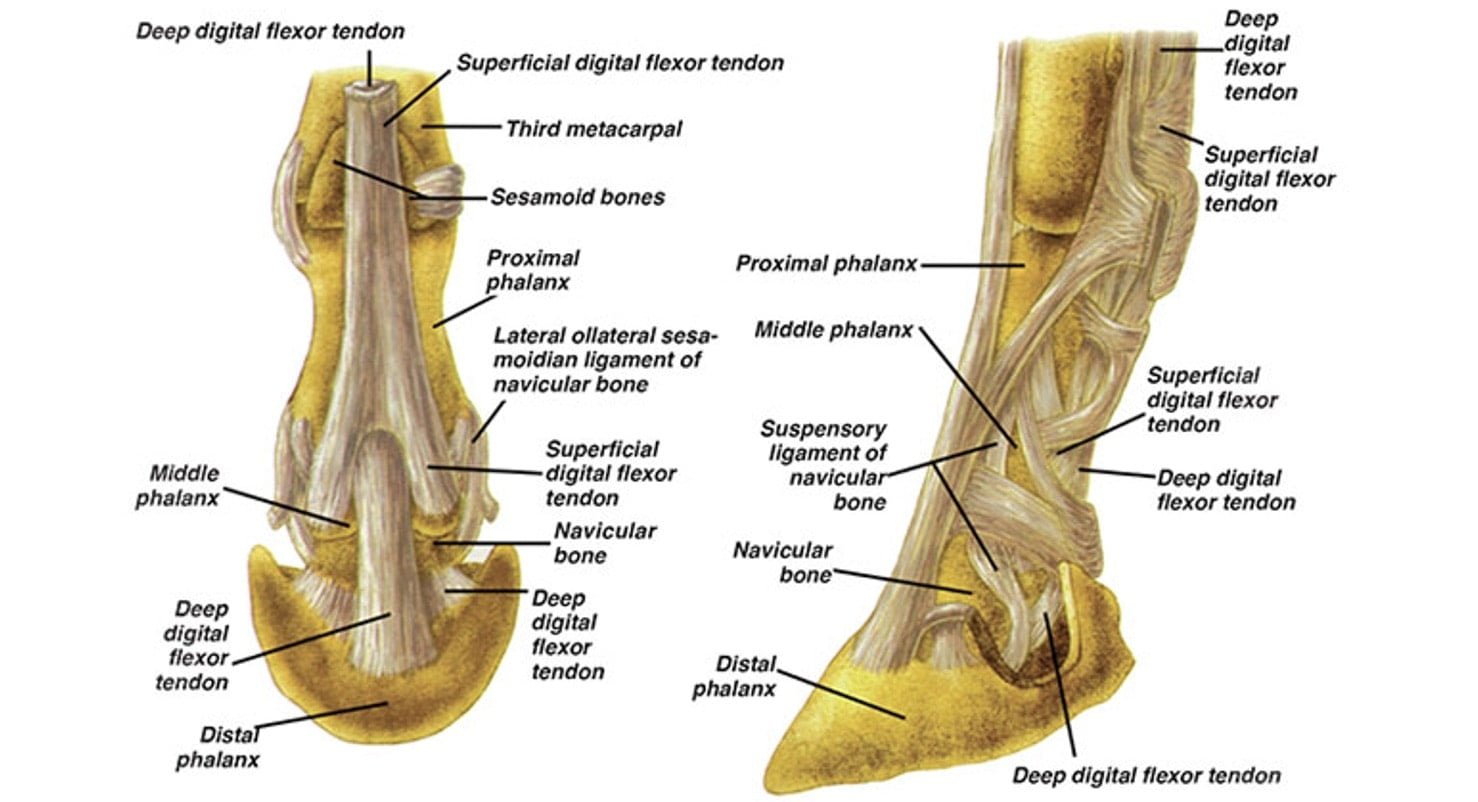

Bone Spur On Navicular Horse . Navicular bone partition is a rare condition reported in horses, which is during the evaluation of a lameness or prepurchase. Xrays show spur on nb probably impeding tendon. The paired suspensory navicular ligaments originate from the dorsolateral and dorsomedial aspects of the proximal phalanx and attach to the proximal navicular border and both extremities. The navicular bone is held in position by three strong ligaments. Navicular in horses relates to problems associated with the navicular bone in the horse’s hoof and is a common diagnosis for lameness in the front foot. Navicular syndrome is a degenerative disease complex of horses that can encompass injuries to any of the structures within the navicular apparatus of the foot, including the navicular bone, navicular bursa, collateral sesamoid ligaments, distal impar ligament, or deep digital flexor tendon. Horse now shod with raised heels/short.

Navicular in horses relates to problems associated with the navicular bone in the horse’s hoof and is a common diagnosis for lameness in the front foot. The navicular bone is held in position by three strong ligaments. The paired suspensory navicular ligaments originate from the dorsolateral and dorsomedial aspects of the proximal phalanx and attach to the proximal navicular border and both extremities. Navicular bone partition is a rare condition reported in horses, which is during the evaluation of a lameness or prepurchase. Horse now shod with raised heels/short. Xrays show spur on nb probably impeding tendon. Navicular syndrome is a degenerative disease complex of horses that can encompass injuries to any of the structures within the navicular apparatus of the foot, including the navicular bone, navicular bursa, collateral sesamoid ligaments, distal impar ligament, or deep digital flexor tendon.

Bone Spur On Navicular Horse Navicular syndrome is a degenerative disease complex of horses that can encompass injuries to any of the structures within the navicular apparatus of the foot, including the navicular bone, navicular bursa, collateral sesamoid ligaments, distal impar ligament, or deep digital flexor tendon. The navicular bone is held in position by three strong ligaments. Navicular in horses relates to problems associated with the navicular bone in the horse’s hoof and is a common diagnosis for lameness in the front foot. Navicular bone partition is a rare condition reported in horses, which is during the evaluation of a lameness or prepurchase. The paired suspensory navicular ligaments originate from the dorsolateral and dorsomedial aspects of the proximal phalanx and attach to the proximal navicular border and both extremities. Horse now shod with raised heels/short. Navicular syndrome is a degenerative disease complex of horses that can encompass injuries to any of the structures within the navicular apparatus of the foot, including the navicular bone, navicular bursa, collateral sesamoid ligaments, distal impar ligament, or deep digital flexor tendon. Xrays show spur on nb probably impeding tendon.